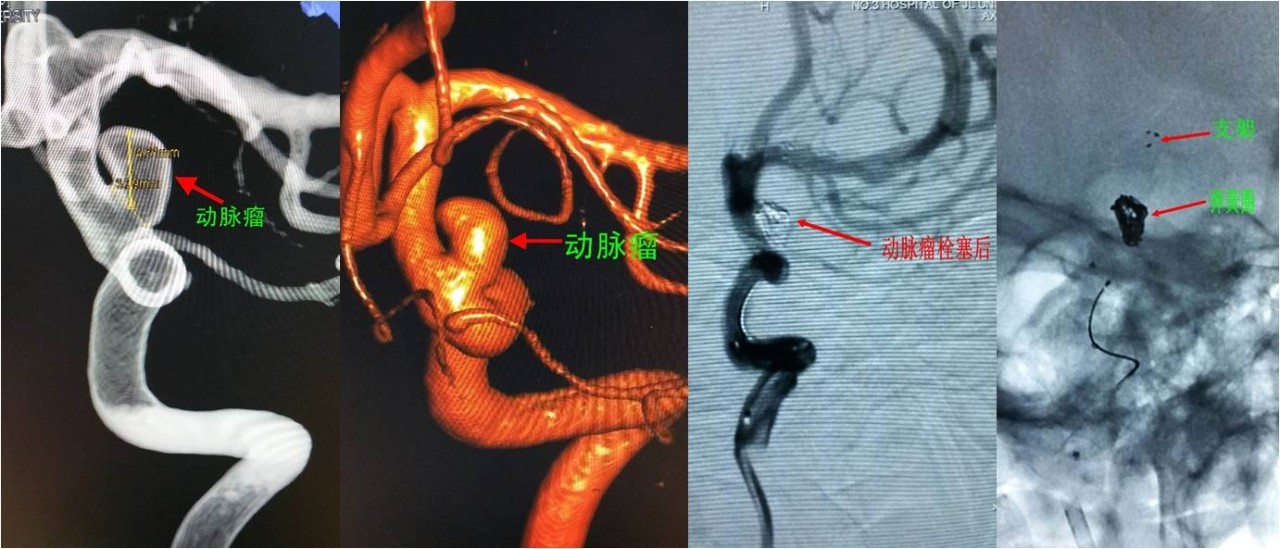

(二)颅内动脉瘤栓塞术

病例1:前交通动脉动脉瘤(Acom-An)

》男性,40岁,因头痛6个月、加重1天入院,头痛为全脑胀痛,疼痛较剧烈,为求进一步诊治就诊于我院门诊,按“头痛待查”收入我院。

》入院时查体:神经系统查体未见阳性定位体征。

》入院后行头颅MRA发现前交通动脉囊状动脉瘤。

病例2:后交通动脉动脉瘤(Pcom-An)

》女性,59岁,因一过性意识不清伴头痛20天入院,头痛为全头炸裂样疼痛,于当地医院检查后诊断为“蛛网膜下腔出血”保守治疗20天,现仍有头痛,为求进一步诊治入院。既往有高血压病病史40年,血压控制不详。

》入院时查体:项强3横指。

术前、术后DSA对比

》DSA检查发现右侧后交通动脉动脉瘤,全麻下行颅内动脉瘤栓塞术。

病例3:后交通动脉未破裂动脉瘤栓塞

》女性,23岁,因间断头痛、头晕6个月,加重2天入院,头痛全脑胀痛,不伴有恶心、呕吐,无耳鸣及听力减退,行头颅CT后按“头痛待查”收入我科。